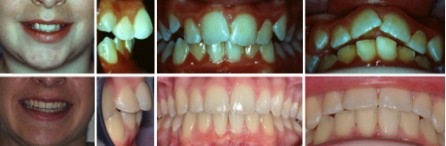

Fall 4: Kopfbiss / Unterkiefervorlage mit seitlich offenem Biss

Therapie: Festsitzende Spange